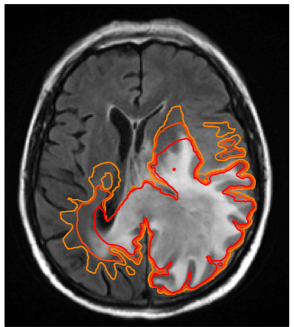

Refer to caption

Figure 8: Multifocal GBM located in the left temporal and frontal lobe: (a) coronal T1 post contrast image; (b) axial T1 post contrast image. The manually drawn CTV is shown in green, the model derived CTV in red.

A.1 Multifocal temporal/frontal lobe case

Figure 8 shows a multifocal GBM case involving the left temporal lobe as well as the frontal lobe. Figure 8a shows the coronal T1 post contrast image, revealing the contrast enhancing tumor mass in the temporal lobe. The axial T1 post contrast image in figure 8b shows the lesion in the frontal lobe. The simulated tumor cell density in figure 9a illustrates several features discussed in sections 3 and 4: The tumor growth model describes the steep fall-off of the tumor cell density in gray matter, leading to differences in the target volume around the lateral sulcus (figure 8b). In addition, modeling tumor cell infiltration through the corpus callosum leads to differences in the target volume in the contralateral frontal lobe. Figure 9 shows the IMRT plan comparison for a homogeneous 60 Gy prescription to the manual CTV (c) and the model-derived CTV (b). The figure shows that the differences in the target volume partly translate into differences in the dose distribution. In particular, the dose difference plot in figure 9d shows a lower dose in the lateral sulcus region for the model-based plan, and a higher dose in the contralateral hemisphere close to the corpus callosum.